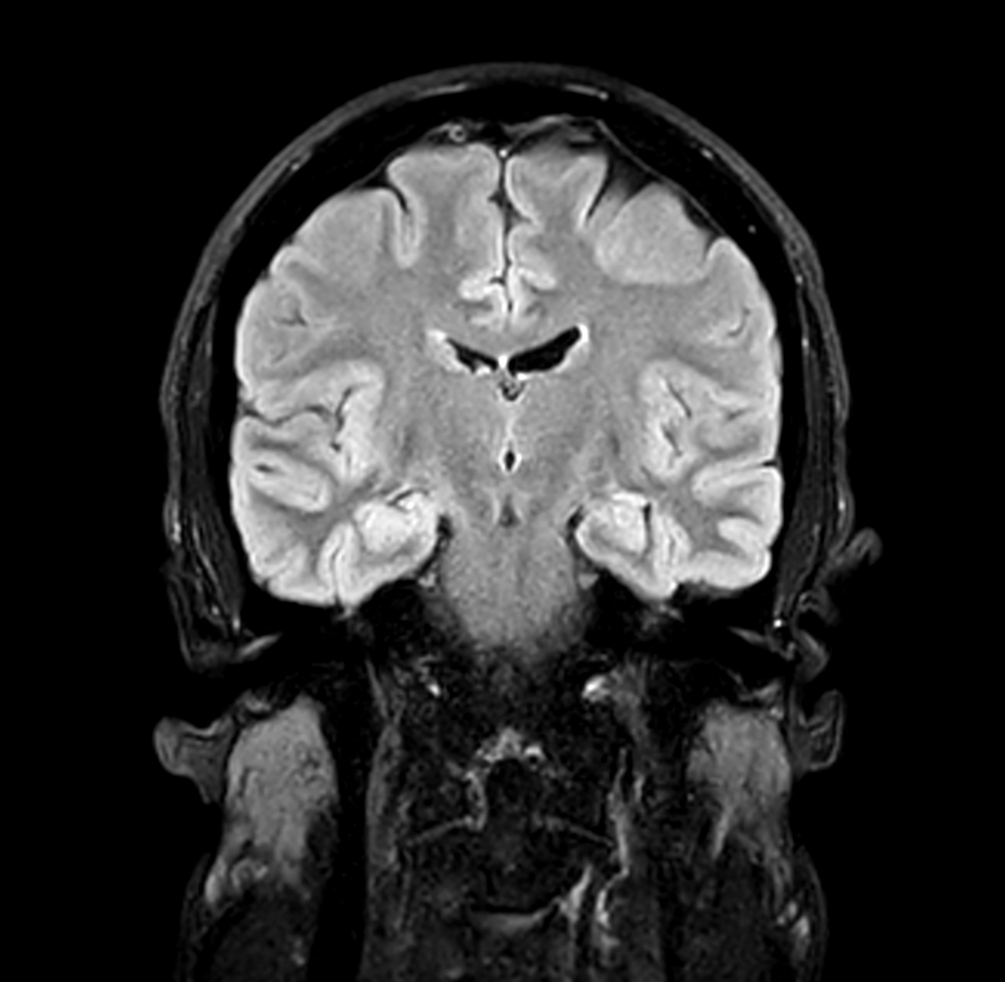

Coronal 3D BrainVIEW FLAIR